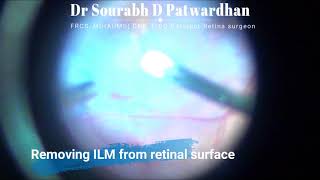

Advanced Diabetic Tractional Retinal Detachment Unimanual Vitrectomy video

Advanced Diabetic Tractional Retinal Detachment - Unimanual Vitrectomy

Advanced Diabetic Tractional Retinal Detachment - Unimanual Vitrectomy Diabetic Tractional retinal detachment treated by vitrectomy